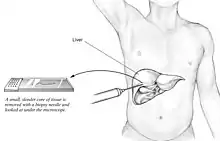

Liver biopsy

A liver biopsy (tissue examination) is the only test widely accepted (gold standard) as definitively diagnosing and distinguishing NAFLD (including NAFL and NASH) from other forms of liver disease and can be used to assess the severity of the inflammation and resultant fibrosis. However, since most people affected by NAFLD are likely to be asymptomatic, liver biopsy presents too high a risk for routine diagnosis, so other methods are preferred, such as liver ultrasonography or liver MRI. For young people, guidelines recommend liver ultrasonography, but biopsy remains the best evidence.[5][7][63][27] Liver biopsy is also the gold standard to detect hepatic fibrosis and assess its progression.[66] Routine liver function blood tests are not sensitive enough to detect MAFLD, and biopsy is the only procedure that can reliably differentiate NAFL from NASH.[16]

There are several liver biopsy techniques available to obtain liver tissue. Percutaneous liver biopsy remains the most common practice. Biopsies can also be performed via the transvenous route, either during surgery or by laparoscopy, especially for people with contraindications to a percutaneous approach. The liver biopsy can also be image-guided, in real-time or not, which is recommended for some clinical situations such as people with known intra-hepatic lesions, previous intra-abdominal surgery who may have adhesions, a small liver that is difficult to percuss, obese people and people with evident ascites. Vital signs must be monitored frequently afterward (at least every 15 minutes in the hour following the biopsy).[66]

According to AASLD guidelines, a liver biopsy may be considered in people with NAFLD who are at increased risk of having steatohepatitis with or without advanced fibrosis, but only when all other competing chronic liver diseases are excluded (such as alcoholic liver disease). The presence of metabolic syndrome, NAFLD Fibrosis Score (FIB-4), or liver stiffness (as measured by Vibration-controlled transient elastography or MRE) can identify the individuals who are at higher risk of steatohepatitis or advanced fibrosis.[5]

For liver fibrosis assessment, percutaneous liver biopsy, with or without image guidance, is contraindicated in uncooperative people.[66] Transjugular liver biopsy is indicated for any person with diffuse liver disease who needs a biopsy but has a contraindication to percutaneous biopsy or needs a hemodynamic evaluation for diagnostic purposes. A transvenous liver biopsy is recommended instead of a percutaneous approach in people with clinically evident ascites, although percutaneous biopsy is an acceptable alternative approach after the removal of ascites.[66]